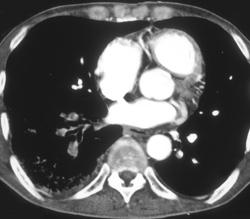

Substernal Thyroid